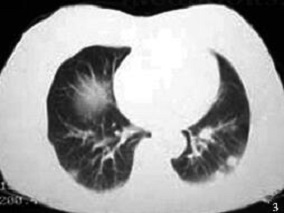

1小时条评论一、病史摘要 患者,女性,61岁,护士,因体格检查发现双下肺多发性小结节状阴影9天于2001年7月18日入院。患者于2001年7月9日体检时,胸片发现左下肺结节状致密影,并于7月14日行肺CT扫描发现双下肺多发性小结节病灶而收住入院。起病后无发热、咳嗽、胸痛及咯血等症...